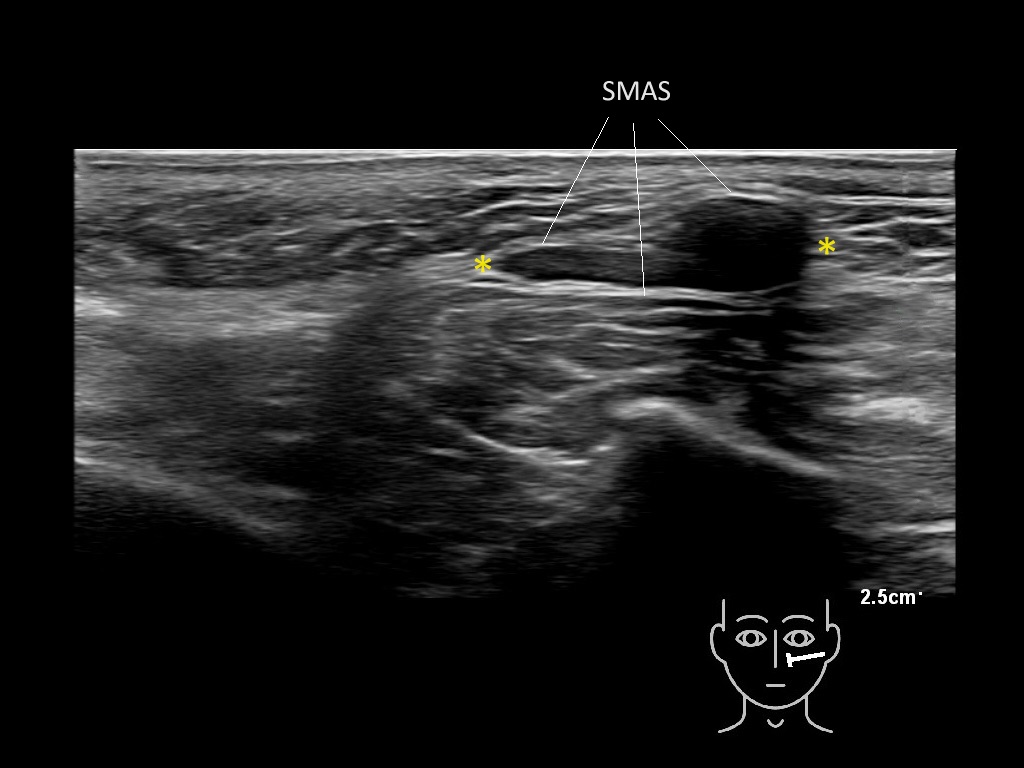

Filler deposits may end up unintentionally in the SMAS or fascial layers of the skin. Very often this will not lead to adverse events, however, adverse events ( nodules, migration / redistribution impaired muscle movement and smiling and malar edema) are are often related to filler ending up in the SMAS or fascia.

Hover over an image to view the secondary image or click on the image title for more information.